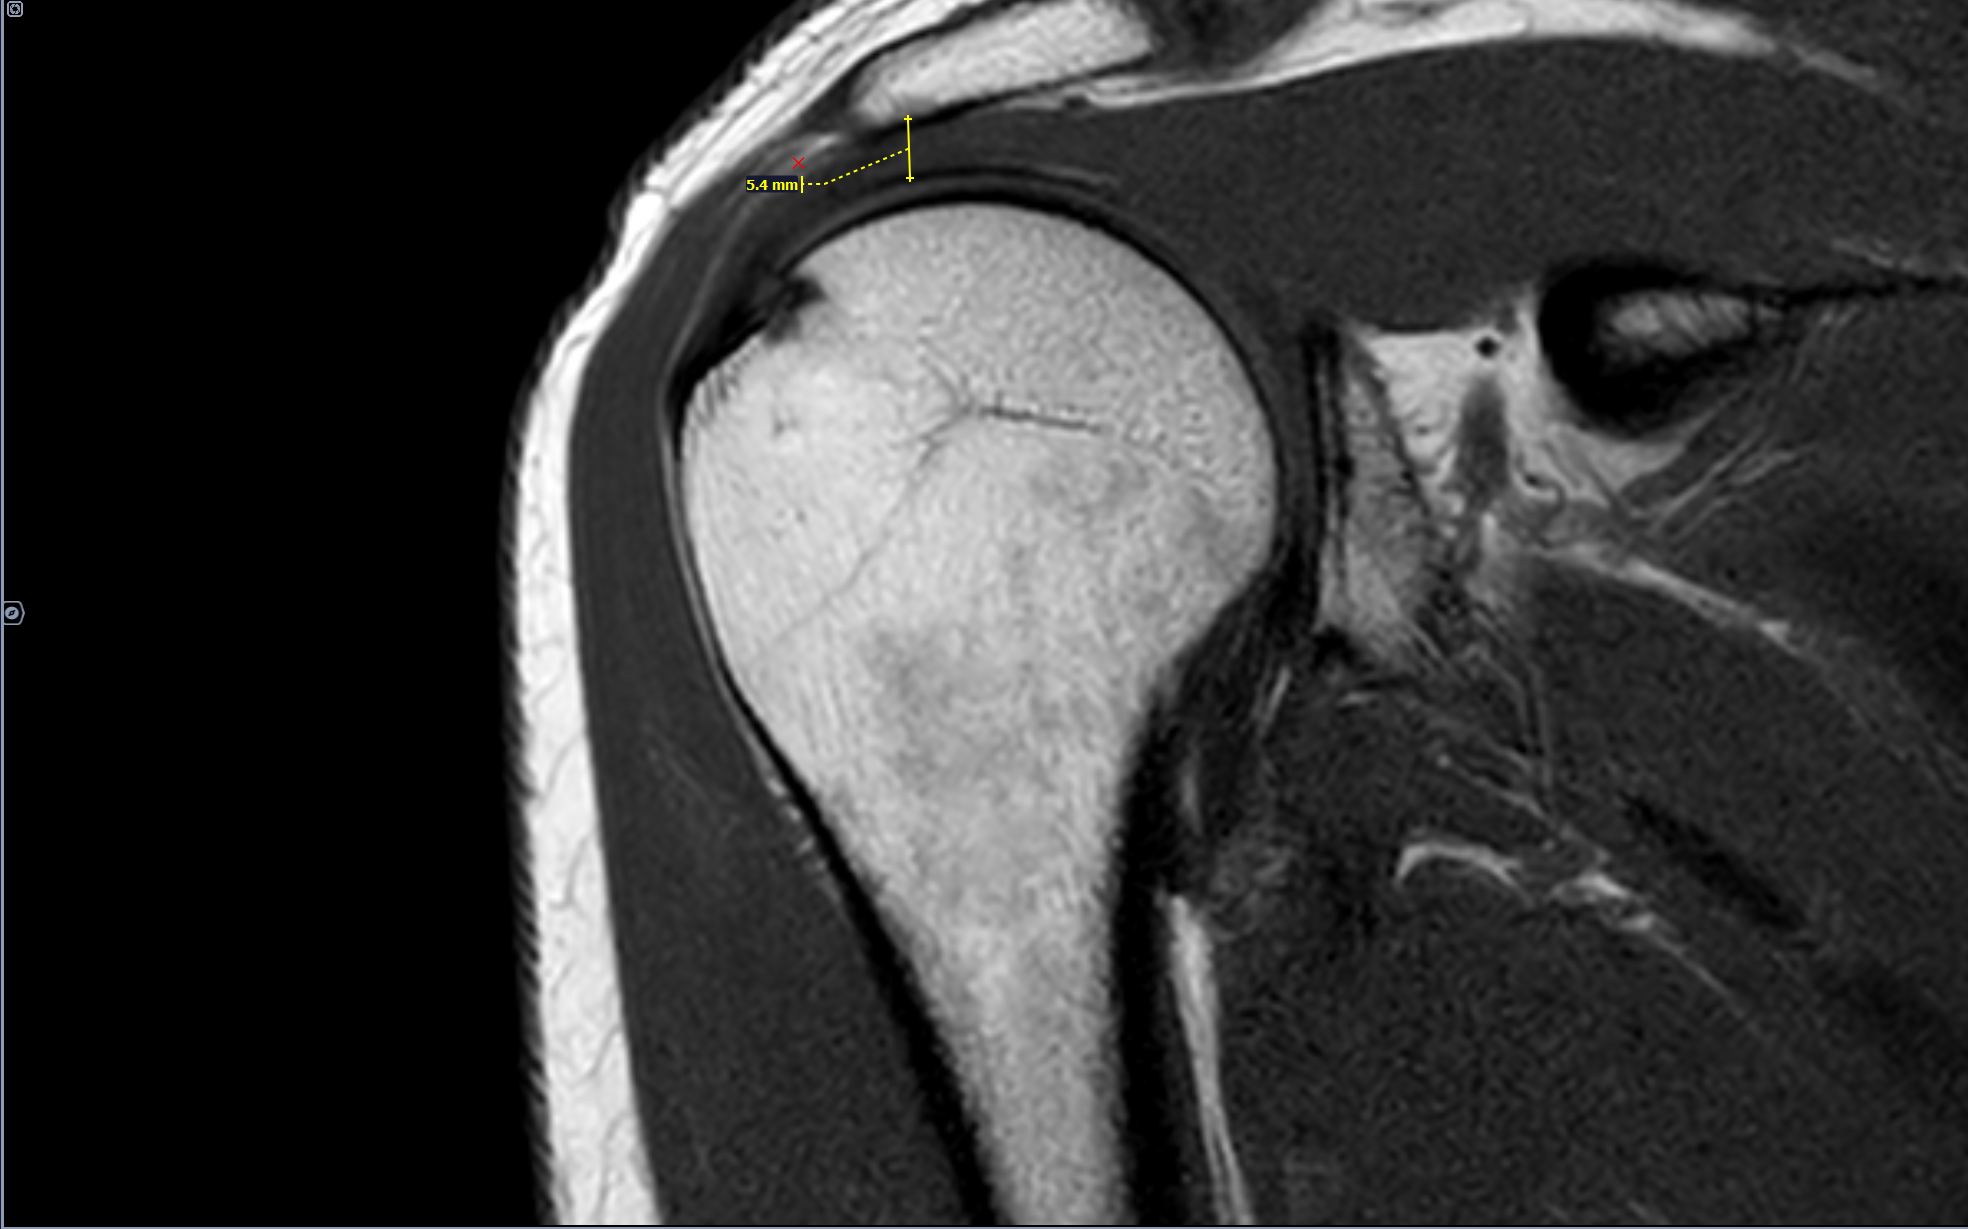

В анамнезе-боли в правом плечевом суставе возникающие при занятии спортом(баскетбол),в последний месяц -сохраняющиеся в покое.

Сужение субакромиального пространства до 5.4мм(норма 7мм),отек суставной поверхности акромиона, в полости субакромиальной сумки- умеренное количество выпота. Заключение: Субакромиальный импиджмент, субакромиальный бурсит правого плечевого сустава.

Категория годности по ст.85(Временные функциональные расстройства костно-мышечной системы, соединительной ткани, кожи и подкожной клетчатки после лечения болезней, ранений, травм, отравлений и других воздействий внешних факторов) Г-временно не годен к военной службе сроком на 3 мес. по I, II, III графам.